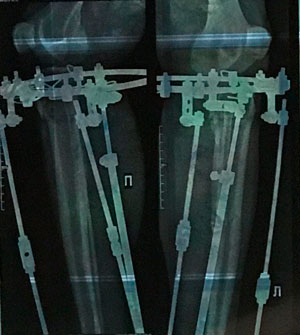

рентген в 60 дней.

IMG_6159-30-09-19-08-16.JPG

IMG_6158-30-09-19-08-16.JPG

IMG_6157-30-09-19-08-16.JPG